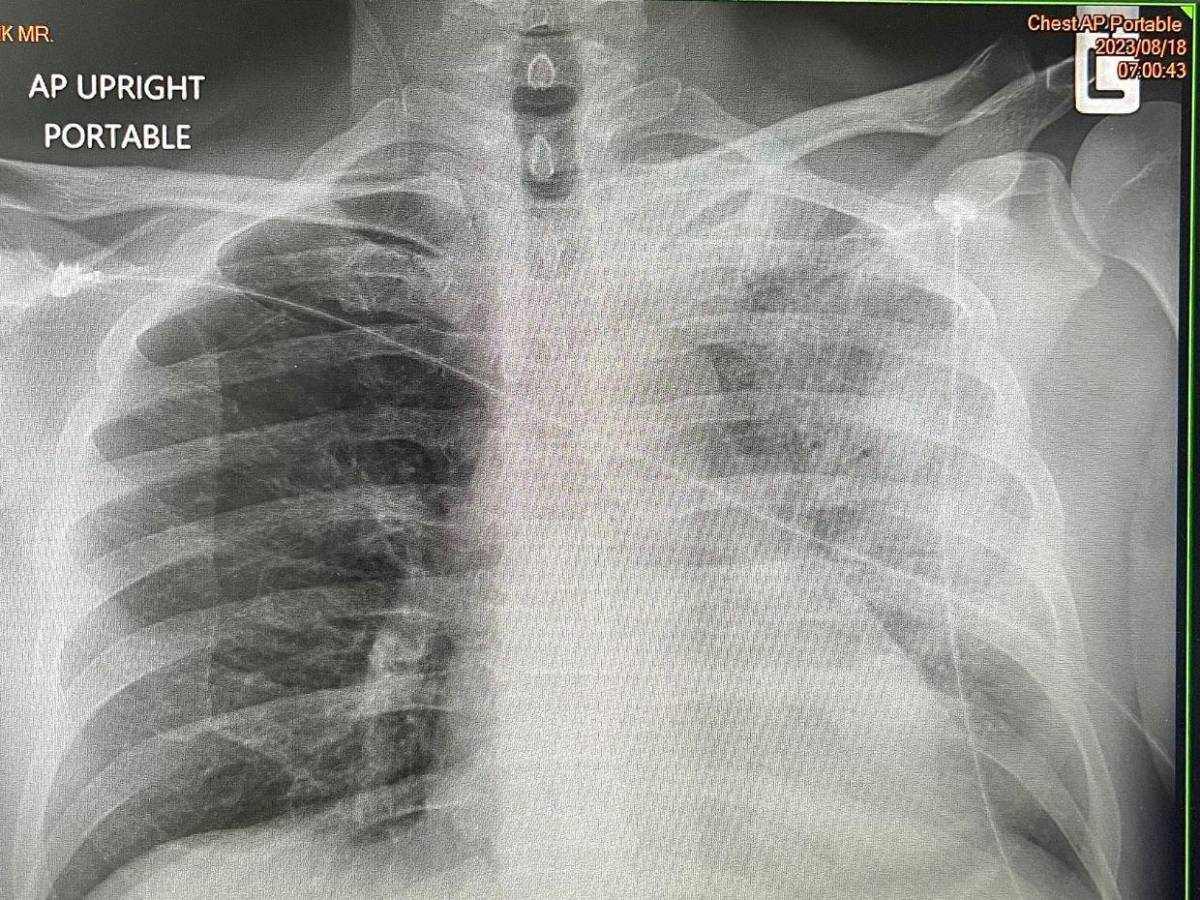

Los síntomas son inicialmente similares a una gripe, que a veces incluye tos seca, fiebre alta (generalmente entre 39 °C y 40 °C), escalofríos, dolores musculares, dolor de cabeza, fatiga y pérdida del apetito. En casos más avanzados pueden presentarse diarrea, confusión o neumonía visible en radiografía.